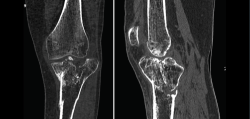

1. Fracturas

Es esencialmente útil en la valoración de los trazos de fractura, de su extensión, del escalón intraarticular y el desplazamiento. También es importante en la planificación del tratamiento de las fracturas intraarticulares complejas.

Los nuevos equipos, con múltiples detectores, permiten realizar cortes finos (submilimétricos) y reconstrucciones en cualquier plano del espacio o tridimensionales (3D) de gran calidad, que facilitan la valoración de estas lesiones(7).

1.2. Tibia (Figura 20)

Figura 20. Corte de reconstrucción coronal de tomografía axial computarizada de rodilla: fractura de ambas mesetas tibiales.